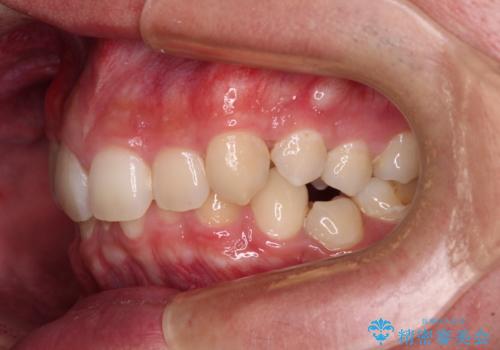

抜歯矯正で叢生と正中のずれを改善|審美装置による矯正症例

- 今回ご紹介するのは、

「全体的なデコボコ(叢生)」「上下の正中のずれ」 を主訴として来院された20代男性の患者様の症例です。

叢生が強く、歯が並ぶスペースが不足していたため、

上下左右の第一小臼歯を抜歯して、矯正治療のための適切なスペースを確保する計画としました。